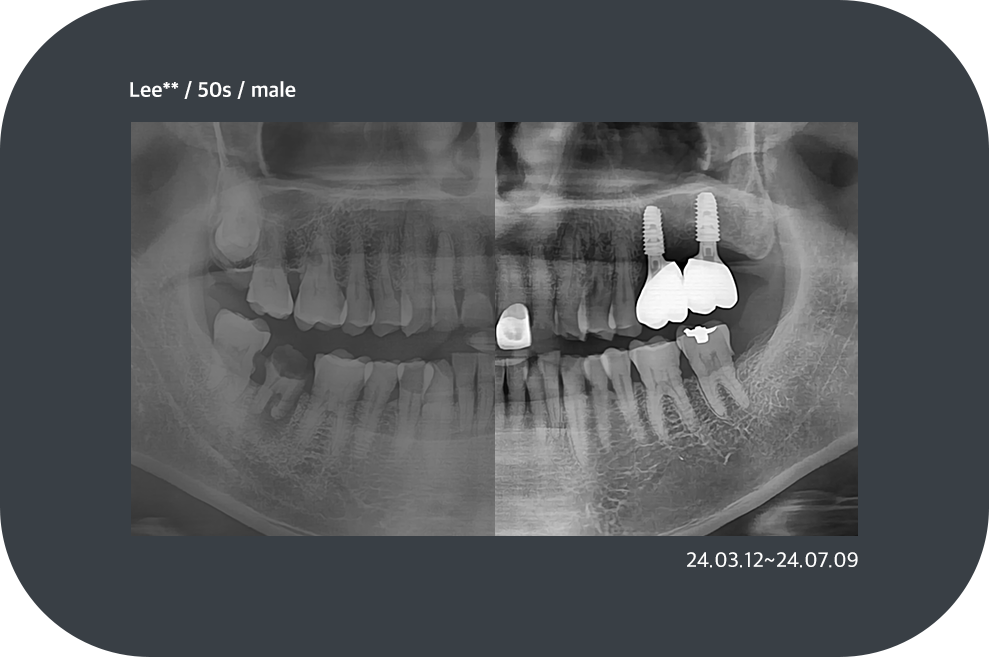

치료사례

임플란트 치료사례

*모든 증례 사진은 의료법 제23조, 제56조에 의거하여, 당사자의 동의하에 게시하였습니다.

*치료 사진은 모두 본원에서 치료한 환자분의 사진입니다.

*치료 사진은 모두 동일인의 사진이며, 동일조건에서 촬영하였습니다.

*개인의 차이에 따라 시술 및 수술 후 부작용이 발생할 수 있으며, 의료진과 충분한 상담을 받으시기 바랍니다.